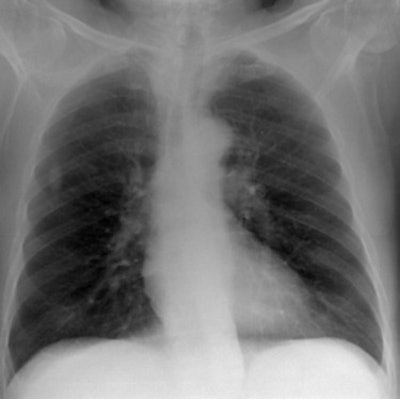

"Many investigators have shown that it is not the system (including quantum) noise that is the limiting factor in chest radiography, but rather the projected patient anatomy or 'anatomical noise.' It therefore follows that any images used to optimize a digital radiographic system for chest radiography must contain clinically realistic anatomical features and noise," Moore and colleagues wrote.

As well as the link between clinical and physical image quality, the results of this paper also demonstrate that chest CR can be carried out with tube voltages much lower than those used traditionally, given that both clinical and physical image quality improve as tube voltage is decreased, he added.

It should be noted that the findings in this paper are specific to CR receptor technology from Agfa HealthCare. However, "given that most powder-based CR phosphors are based on the barium fluorohalide family, it is likely that the conclusions of this work are transferable to other manufacturers, but further studies would be worthwhile," Moore and colleagues wrote in the study.